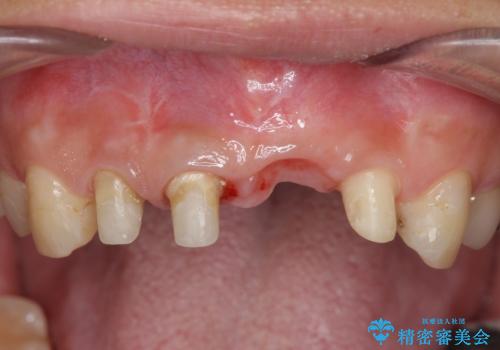

不良インプラントを除去し最終的にブリッジによる補綴で審美性の改善を行うこと、その準備として骨の造成・歯肉の移植による歯の欠損部顎堤のボリュームを維持・増大を計画します。

より審美的な改善を強く求められたため、インプラントを除去し可及的に欠損部顎堤を増大したのちブリッジによる審美改善を行いました。